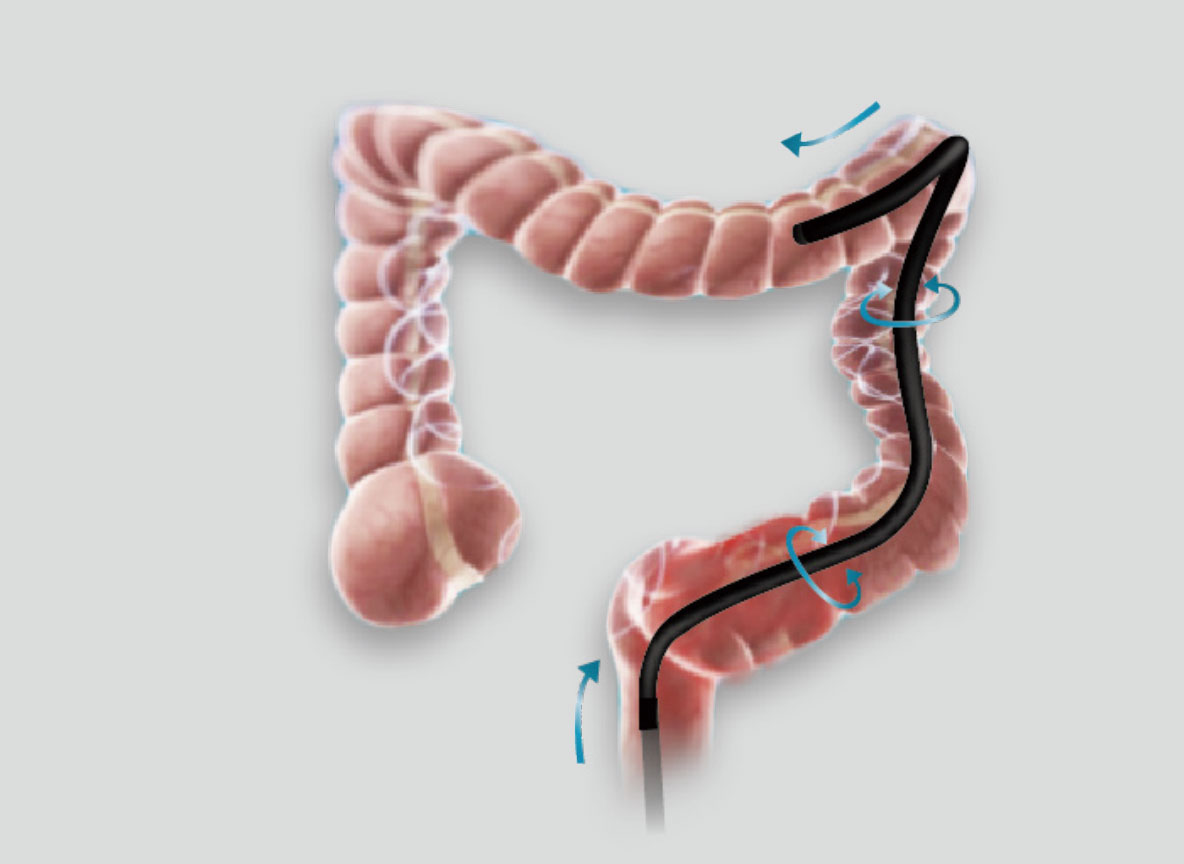

弯曲角度大,方便观察食管下段贲门、胃底部等难以观察到的部位,减少盲区。

带来镜体插入及诊疗新体验。

操作部轻量化设计,按钮布局合理,操作便捷。

在临床操作中,时刻保持黏膜清洁和视野清晰,更快寻找出血点,满足临床治疗。